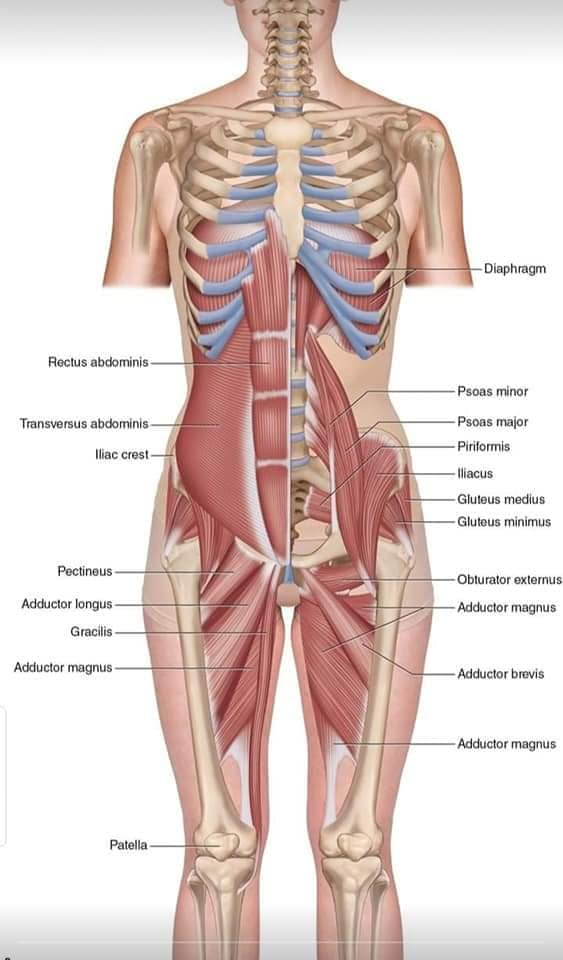

Скелетно-м'язова система людини (синоніми: Опорно-рухова система, опорно-руховий апарат, кістково-м'язова система, локомоторна система) — комплекс структур який утворює каркас, надає форму організму, дає йому опору та забезпечує захист внутрішніх органів і можливість пересування у просторі. Це функціональна сукупність кісток скелета, їх з'єднань (суглобів і сінартрозів), і соматичної мускулатури з допоміжними пристосуваннями, які здійснюють за допомогою нервової регуляції локомоції, підтримання пози, міміки та інших рухових діях, поряд з іншими системами органів утворює людське тіло.

Це саморушний механізм, який складається з 400 м'язів, 206 кісток і декількох сотень сухожиль. Більшість кісток скелету з'єднане рухомо за допомогою суглобів. Одним кінцем м'яз прикріплюється до однієї кістки, утворюючи суглоб, іншим кінцем — до іншої кістки. В англомовній літературі застосовують близькі за значенням терміни: англ. musculoskeletal system (скелетно-м'язова система) та англ. locomotor system (локомоторна система).

М'язова система людини є однією з основних систем організму, що відповідає за рухи, підтримання пози та стабільність. Вона складається з понад 600 м'язів, які можна класифікувати на скелетні, гладкі та серцеві м'язи. Скелетні м'язи, які є об'єктом нашого детального розгляду, дозволяють контролювати навколишній світ і виконувати різноманітні рухи. Особливу увагу в нашій статті буде приділено шейним і спинним м'язам, оскільки ці групи м'язів мають критичне значення для підтримання правильного постава та функціонування хребта.

Спинні м'язи

Спинні м'язи виконують функції підтримки хребта, а також дозволяють здійснювати рухи тулуба.

Глибинні спинні м'язи

М'язи, що забезпечують стабільність хребта: М'язи, що розташовані між хребцями: включають мускулатуру, яка забезпечує стабільність і підтримку хребта, а також дозволяє здійснювати рухи хребта.

М'язи, що здійснюють ротацію та нахили

М'язи, що забезпечують ротацію хребта: Ротаційні м'язи: допомагають у здійсненні обертальних рухів тулуба, а також у підтримці рівноваги і стабільності хребта.